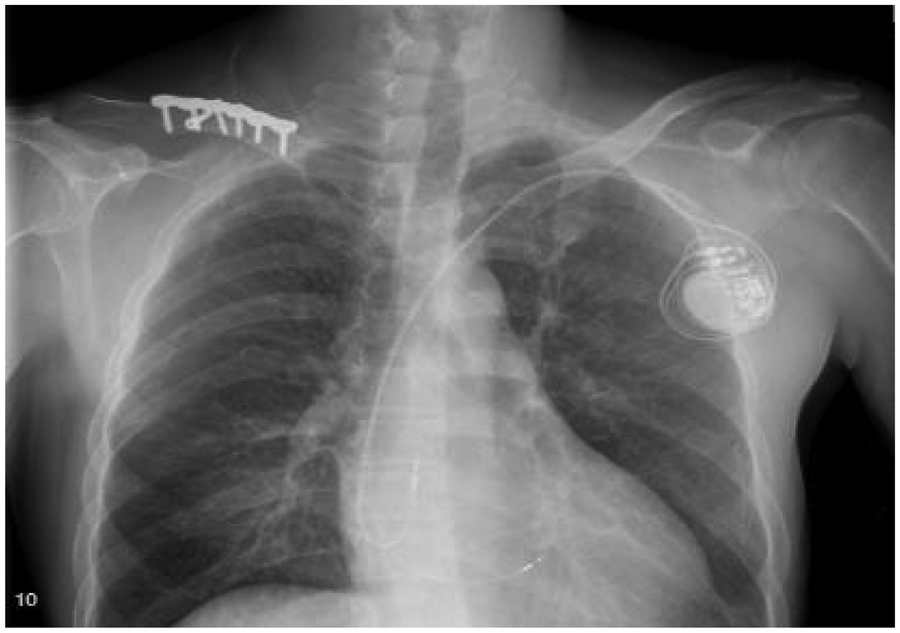

Treatment for the patient began on two weeks later. The first course of treatment using the VSD regimen (bortezomib 2.3 mg + cyclophosphamide 1.2 g + dexamethasone 40 mg) showed poor efficacy. The treatment was then changed to the DVCD regimen (bortezomib 2.3 mg + daratumumab 800 mg + cyclophosphamide 0.5 g + dexamethasone 40 mg). Due to persistently high heart rate after chemotherapy, the patient exhibited atrial flutter and paroxysmal atrial fibrillation on ECG, with a programmed AT/AF burden of 4%. Following chemotherapy, the patient developed persistent tachycardia accompanied by atrial flutter and paroxysmal atrial fibrillation. Despite receiving standard anticoagulation, electrical cardioversion, and diuretic therapy, serial follow-up visits revealed persistently elevated BNP levels. These findings suggested the possible presence of occult arrhythmias that had not been adequately captured or assessed by conventional electrocardiographic monitoring.Given the diagnosis of systemic AL-CA—a condition known to predispose the cardiac conduction system to infiltration by amyloid deposits—the patient was at significantly increased risk for developing advanced atrioventricular block, prolonged asystolic pauses, and even sudden cardiac death. However, at that time, there were no clear indications warranting immediate implantation of a permanent pacemaker or an implantable cardioverter-defibrillator (ICD). Therefore, to establish a definitive causal relationship between the patient's symptoms and potential arrhythmic events, and to enable precise risk stratification without premature device intervention, the clinical team decided to implement long-term, continuous outpatient cardiac rhythm monitoring. Accordingly, an implantable cardiac monitor (ICM) was implanted two months after the initiation of systemic therapy to objectively detect and evaluate potentially life-threatening bradyarrhythmias or tachyarrhythmias. One year later, the patient received HD-Mel conditioning (melphalan 150 mg on day 1, 100 mg on day 2, with supportive liver and stomach protection, antiemetic, prophylactic antimicrobial, and antithrombotic therapies) followed by autologous peripheral blood hematopoietic stem cell transplantation. Maintenance therapy with daratumumab was continued post-transplant. Subsequently, the patient's dFLC levels were normalized (1.35 mg/L) and stabilized. Echocardiography showed that the ventricular muscle had become thinner compared to before (LVPWd 1.16 cm, right ventricular free wall 0.45 cm), with left ventricular systolic function within the normal range (EF: 57%) and mildly reduced left ventricular diastolic function (grade 1), LV GLS = −10.4% (Figure 8). This year, the patient presented again with “dizziness and chest tightness for one week, accompanied by two episodes of syncope.” ICM interrogation revealed paroxysmal atrial fibrillation with a 7-s pause (Figure 9), prompting implantation of a permanent pacemaker (Figure 10). Since implantation of the dual-chamber pacemaker, the patient has not experienced any further episodes of syncope, and exercise tolerance during daily activities has significantly improved. We programmed the pacing rate at 80 beats per min. As of the time of manuscript submission, the patient had no recurrence of atrial fibrillation–related symptoms, and ambulatory electrocardiographic monitoring showed no frequent or rapid atrial arrhythmias.

Figure 10

The patient underwent pacemaker implantation with left bundle branch pacing.

AL amyloidosis leads to diffuse myocardial infiltration, ventricular wall stiffening, and restrictive cardiomyopathy, which is a pathophysiological state that is highly sensitive to ventricular electromechanical synchrony. Conventional right ventricular apical pacing (RVP) often results in a non-physiological sequence of ventricular activation, causing significant electromechanical dyssynchrony that may further exacerbate diastolic dysfunction, reduce cardiac output, and accelerate the deterioration of heart function. In contrast, left bundle branch pacing (LBBP) directly captures the His-Purkinje conduction system, enabling a more physiologic pattern of ventricular depolarization and contraction. This approach effectively preserves ventricular synchrony and thereby mitigates the risk of pacing-induced ventricular remodeling. In this patient, clear evidence of myocardial involvement was already present prior to pacemaker implantation (LVEF was 47.8%, and GLS was markedly reduced at −6.2%), indicating borderline systolic function. Given the underlying disease process, which commonly causes conduction system infiltration and predicts a high burden of future ventricular pacing, the team opted for LBBP during the procedure. This strategic decision aimed to ensure reliable pacing support while maximizing the preservation of ventricular synchrony, thereby preventing pacing-induced cardiomyopathy and optimizing long-term outcomes.Given the myocardial stiffness and severely impaired diastolic function caused by cardiac amyloidosis, the patient's stroke volume was markedly reduced, rendering cardiac output highly dependent on heart rate for compensation. Therefore, the pacemaker's lower rate limit was programmed to 80 beats per min to moderately increase heart rate, thereby maintaining adequate cardiac output and improving hemodynamic status. Additionally, this relatively higher pacing rate may have exerted an anti-arrhythmic effect, which potentially by suppressing atrial electrical instability and reducing long pauses, consistent with the concept of “pacing-mediated suppression of atrial fibrillation”. Post-implantation follow-up confirmed the absence of atrial fibrillation–related symptoms, and ambulatory electrocardiographic monitoring revealed no frequent or rapid atrial arrhythmias.